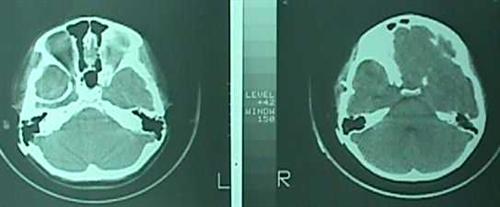

* Arka çukur (posterior fossa) araknoid kistleri

Bu kistler beyin sapı-beyincik bileşkesinde (Resim 10), beyincik arka kısmında (Resim 11) veya dördüncü karıncık içinde (Resim 12) yerleşirler. Beyincik arkasındaki ve veya dördüncü karıncık içindeki kistler hidrosefaliye yol açarlar. beyin sapı-beyincik bileşkesindekiler ise burada bası yaptıkları organ ve kafa sinirlerine göre baş ağrısı, baş dönmesi, bulantı-kusma, yutma güçlüğü ve dengesizlik gibi yakınmalara neden olurlar.

Arka çukur yerleşimli araknoid kistlerin tedavilerinde çoğunlukla açık cerrahi ve şant uygulanmaktadır. Endoskopik ameliyatlarda sınırlı deneyimler bulunmaktadır.

Resim 10: beyin sapı-beyincik bileşkesinde araknoid kist (

*).

Resim 11: (a) BT’lerde ve

(b) dikey MRG kesitlerinde beyincik arkasında yerleşim gösteren araknoid kist.